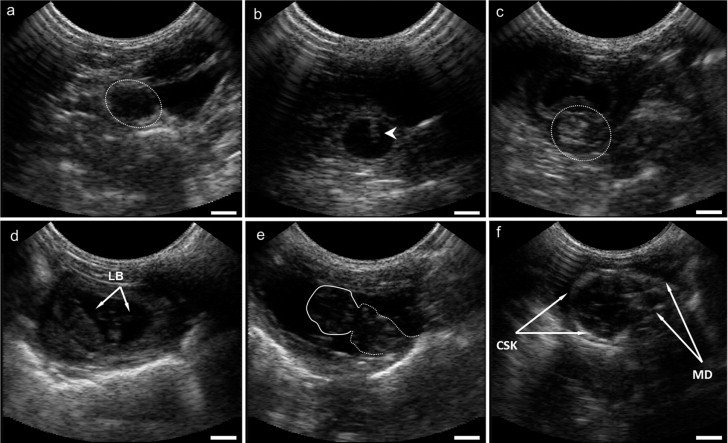

اکوکاردیوگرافی قلب جنین (Fetal Echocardiography) یک روش تخصصی سونوگرافی است که برای بررسی دقیق ساختار قلب جنین، حفرهها، دریچهها و جریان خون در قلب و عروق اصلی مورد استفاده قرار میگیرد. این روش معمولاً در هفتههای ۱۸ تا ۲۴ بارداری انجام میشود و میتواند مشکلات مادرزادی قلبی را در مراحل اولیه تشخیص دهد.

- پزشک حفرههای قلب، دریچهها و جریان خون را بررسی میکند.